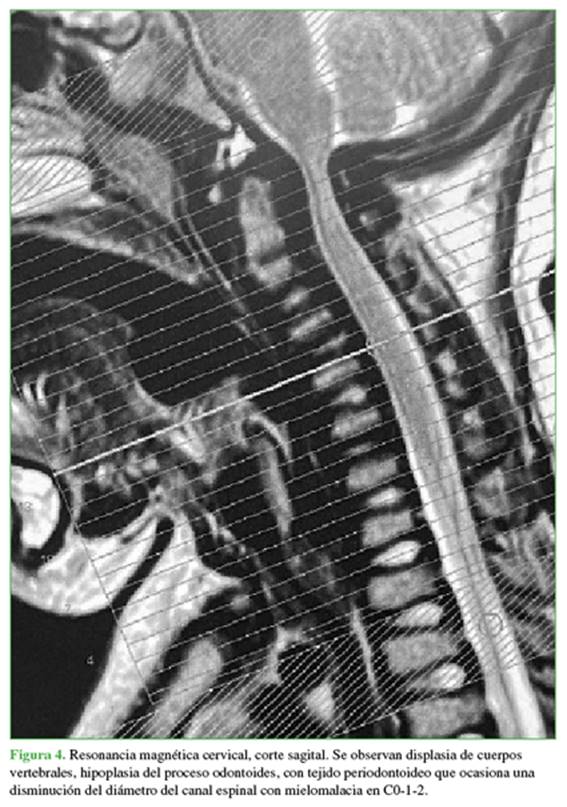

La tomografía computarizada y la resonancia magnética (RM), realizadas en decúbito dorsal, mostraban variedades morfológicas de C1 a C5, con disminución de la altura de los cuerpos vertebrales (hipoplasia), principalmente en C3-4-5, hipoplasia de odontoides y tejido periodontoideo que causaba una disminución del diámetro del canal cervical a ese nivel; y mielomalacia en C0-1-2 (Figuras 3-5).